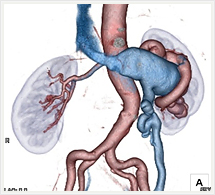

腹部・腹部血管

門脈(黄)

画像紹介(ステントグラフト編)

ステントグラフトは、人体に馴染みやすい人工布を筒状に形成し、これにステントといわれるバネ状の金属を縫い付けた人工血管で、これをストロー状のチューブで、患者さんの太ももの付け根から動脈内に挿入します。ステントグラフトを動脈瘤のある部位まで進め動脈瘤の内側ステントグラフトを挿入します。そうすることで動脈瘤の拡大を抑え、動脈瘤が拡大しなければ破裂する危険性がなくなります。このように、ステントグラフトによる治療は外科手術に比べて切開部が小さく、身体への負担が極めて少ない低侵襲血管内治療です。

ステントグラフト挿入術直後の造影